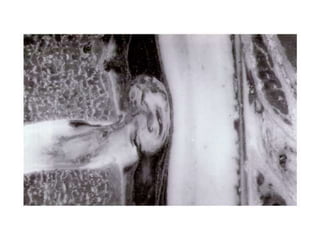

Axonal Regeneration

 PERIPHERAL - Schwann cells

promote growth of nerve fibers

 CNS - Oligodendrocytes inhibit

growth of axons

Axonal Regeneration  PERIPHERAL- Schwann cells promote growth of nerve fibers  CNS - Oligodendrocytes inhibit growth of axons